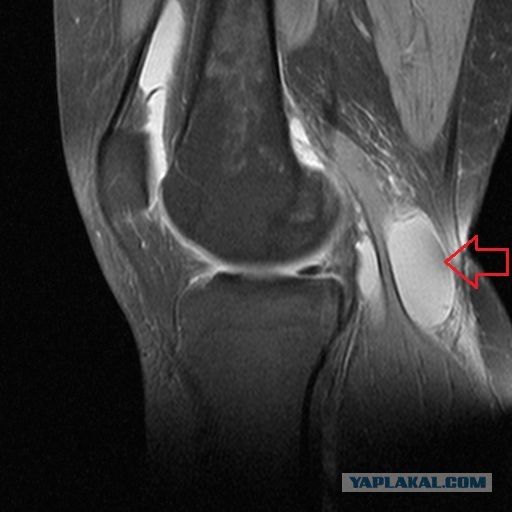

Фото и диагностика кисты Бейкера